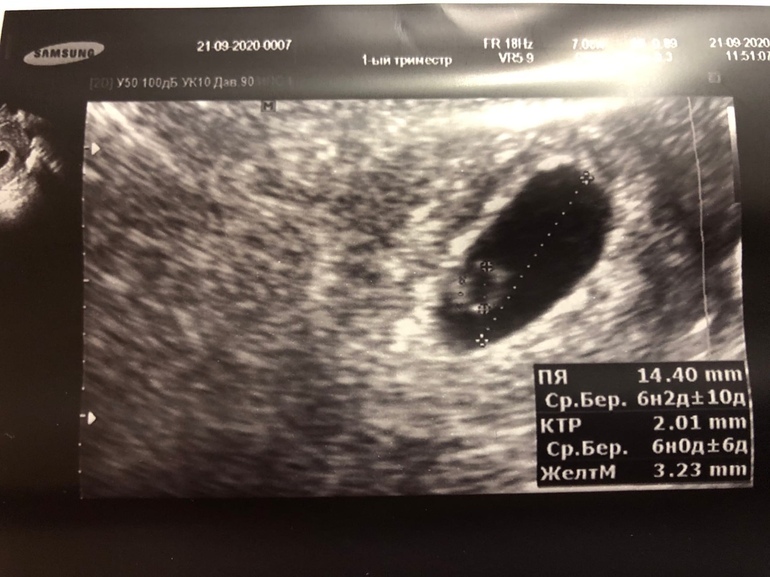

Нам 6+2

Кунжутину нашли ровно в 6 недель.

А пока вот фоточка нашего колечка с бриллиантом!